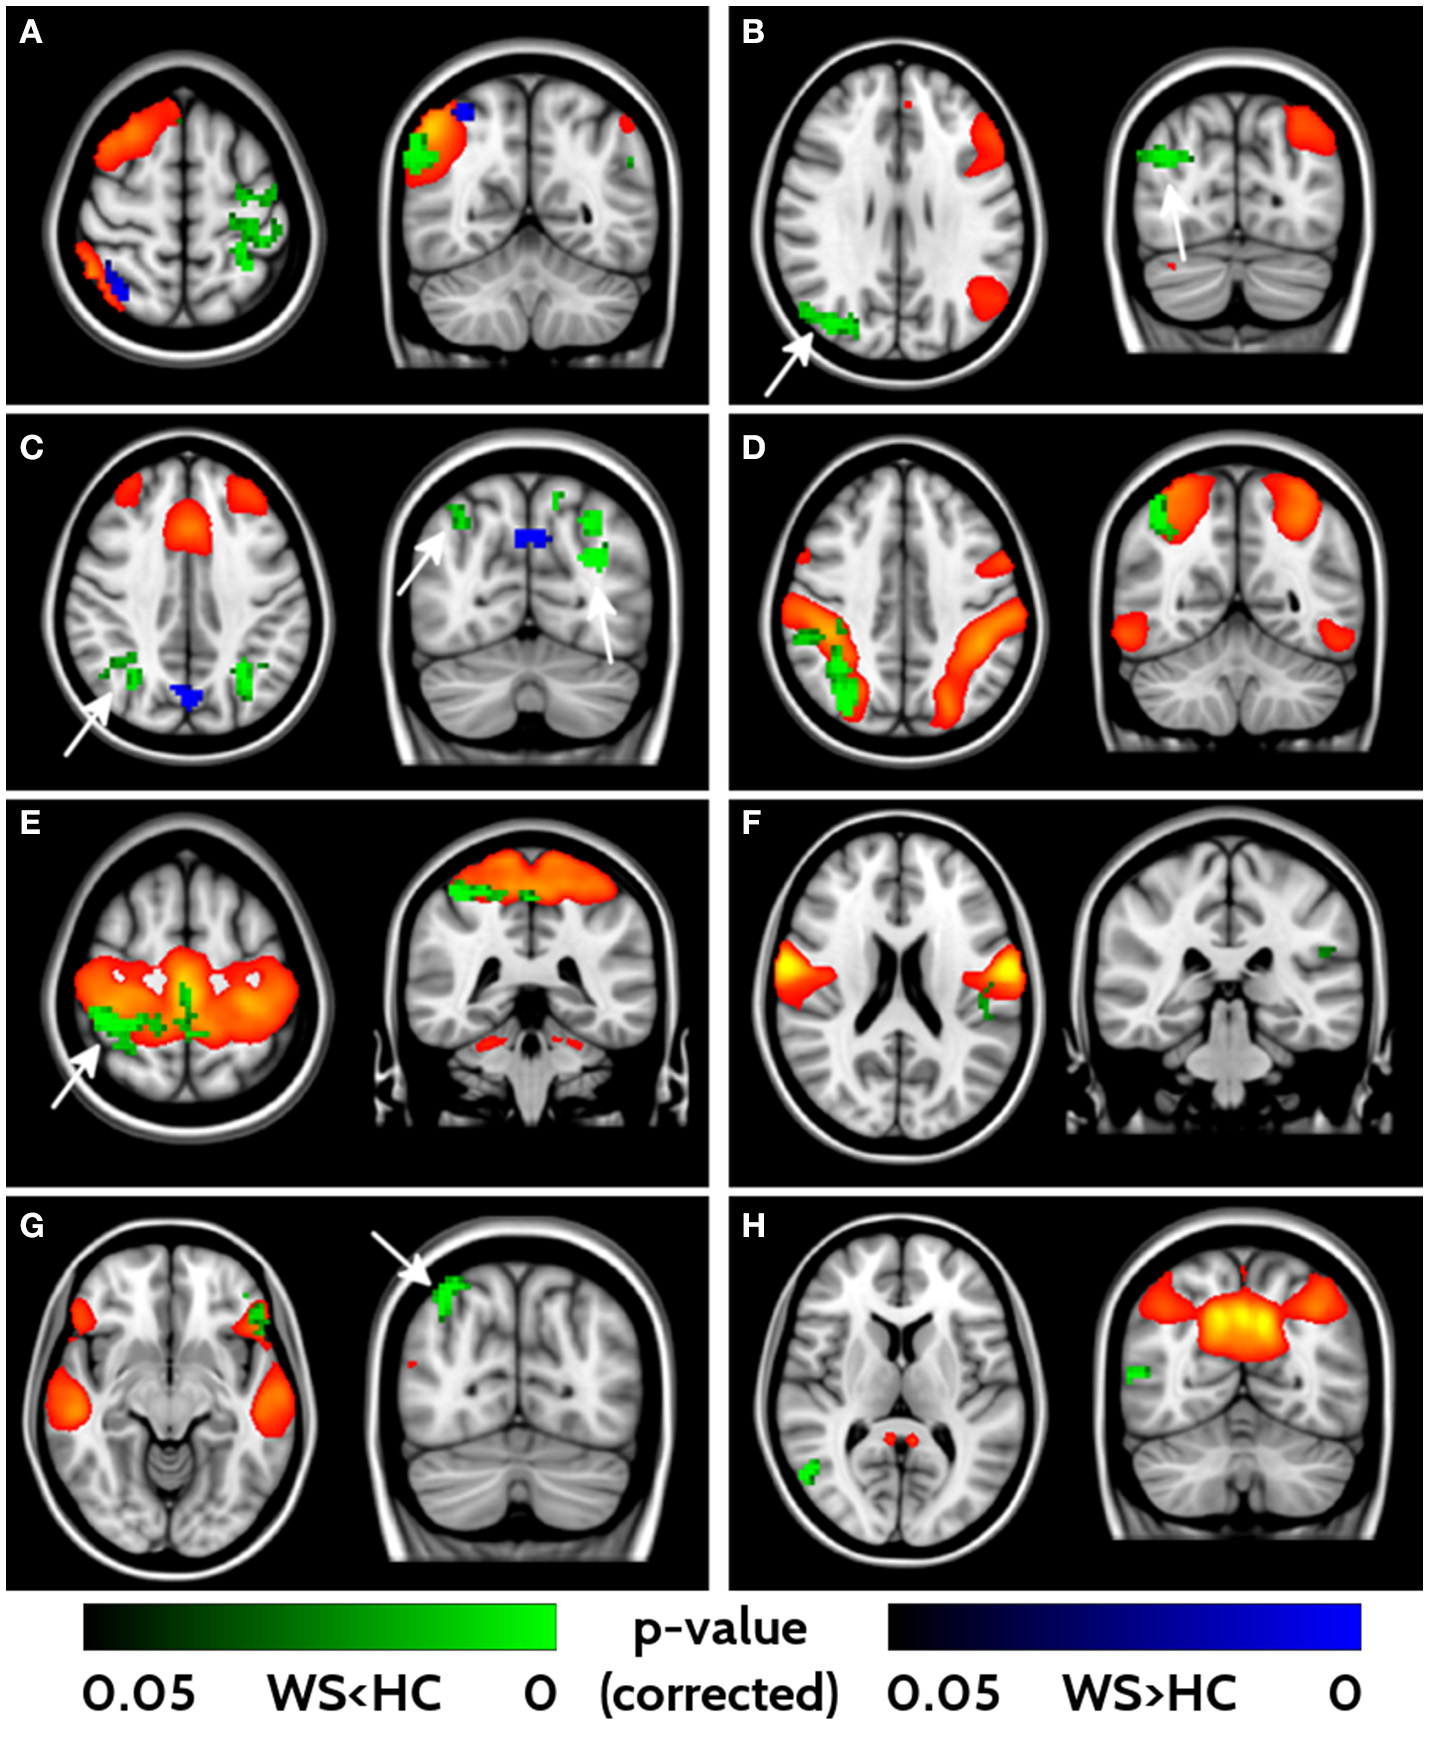

fMRI

With the fMRI analysis, we tested for group differences in FC within the 16 networks identified with ICA. Eight out of sixteen components revealed different FC between WS patients and HCs (Figure 3). All the significant networks (right and left fronto-parietal, executive control, dorsal attention, anterior, and posterior sensori-motor, ventral stream and default mode networks) showed areas of lower FC in WS patients compared to HC, with only two (right fronto-parietal and executive control networks) showing also small clusters of higher connectivity in the WS patients group. Areas of lower connectivity for WS patients were mainly located in bilateral parieto-occipital lobes (Cuneus, Precuneus and Superior Occipital cortex) and posterior frontal cortex. Smaller areas of lower connectivity were also located in ventrolateral prefrontal cortex and lateral parietal cortex.

Figure 3

Impaired functional connectivity in WS patients. Right- and left-frontoparietal networks (A, B), executive control network (C), dorsal attention network (D), sensorimotor networks (E, F), ventral stream (G) and default mode networks (H) showed significant differences in functional connectivity between WS and HCs. Yellow/red voxels represent the areas involved in each network. Areas of lower functional connectivity (FC) in WS patients compared to HCs are shown in green, whereas areas of higher FC in WS patients compared to HCs are shown in blue. Arrows point at bilateral parieto-occipital clusters characterized by impaired FC. Significance level is set at p < 0.05 corrected for multiple comparisons.

The analysis of resting state fMRI showed an overall lower functional connectivity in our WS group compared to HCs in many significant brain networks. Among the few previous studies in literature, Vega et al. (21) described increased (compared to controls) between-network connectivity in the fronto-parietal DMN in their group of WS patients while Sampaio et al. (22) found a decreased FC in the posterior hub of the DMN. This modification has been putatively related with both immaturity of the brain and with the singularity of the WS behavioral phenotype. However, differences in FC in the DMN and/or fronto-parietal networks are not specific of WS and have been reported in other neurodevelopmental disorders [e.g., autism (40), ADHD (41), Down syndrome (42)] and may underlie an impaired ability to integrate information from distant brain regions into coherent distributed networks.